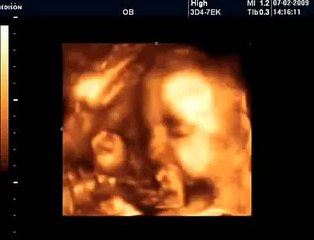

18 Haftalık Gebelik Bebek Ultrason Görüntüsü

Hafta hafta gebelik dönemi 18 haftalık bebek ultrason görüntüsü. Gebelikte 18. hafta daha çok bilgi için sayfamızı ziyaret edebilirsiniz.